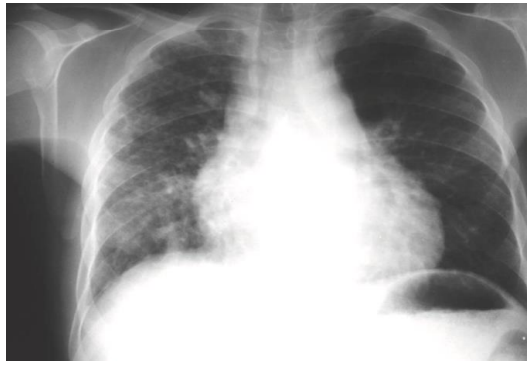

Jonas, 17 anos, portador de drepanocitose, comparece ao pronto atendimento com

relato de dor torácica, taquipneia, febre, tosse e dispneia. Ao exame clínico, ausculta pulmonar sem ruídos adventícios. FR 26 irpm, oximetria 92% em ar ambiente.

Laboratório evidenciou leucocitose. Radiografia de tórax segue abaixo: